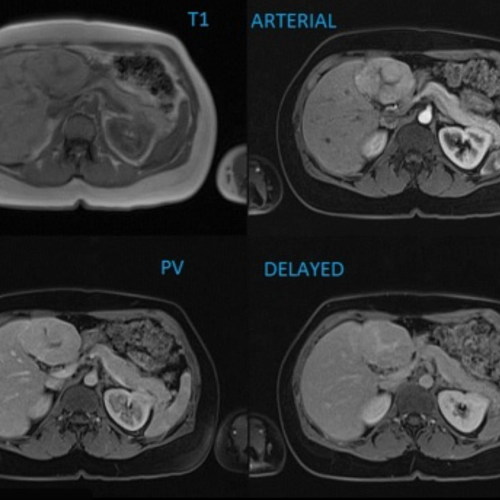

CASO 3

Donna di 32 anni, incidentaloma epatico di 4 cm. APR: Nessuna epatopatia, nessuna cirrosi. Assume contraccettivi orali.

Quale caratteristica permette di distinguere questa lesione da un adenoma epatico?

Risposta esatta: D

FNH:

Si tratta di iperplasia nodulare focale (FNH).

La chiave è la fase epatobiliare:

- La FNH contiene epatociti funzionanti → capta il mezzo di contrasto epatospecifico

- L’adenoma generalmente appare ipo-intenso in fase epatobiliare

La cicatrice centrale aiuta, ma non è sempre presente.

L’enhancement arterioso non è discriminante (anche l’adenoma è ipervascolare).